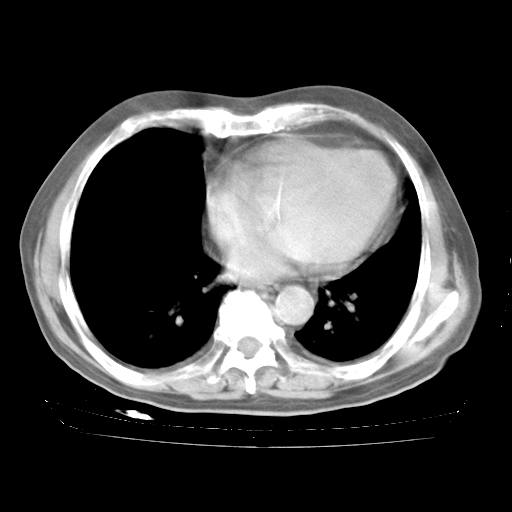

4月28日肺部CT——再次出现类似去年5月9日——透光度降低,“间质性”改变。